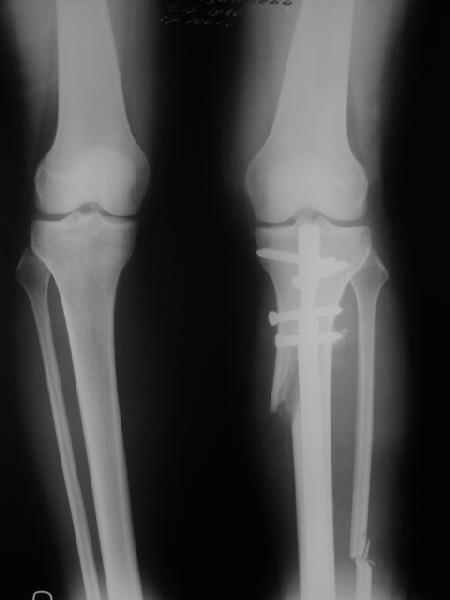

Yesterday i performed correction of one leg (the plan to make both in one session was cancelled because of some external reasons). Suggestions of Nuno Lopes were most close to my view. A small wire distractor was used intraoperatively. Derotation ~6-7 degrees was performed also. CT scans evaluating rotation will be available only

tomorrow. No problem to change rotation of the operated limb in the moment of the second surgery. Comments/critics are welcome.

Can the attached result be analyzed by the software?